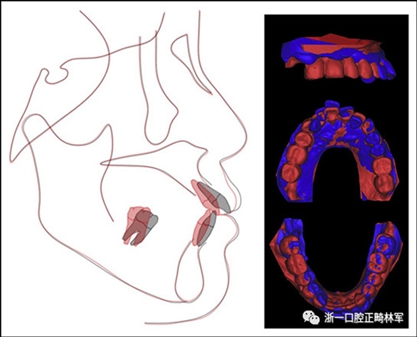

治療后頭影測量分析顯示上頜切牙的傾斜和唇部相對于E線的位置都得到改善(表II)。治療前后頭影測量圖的疊加顯示上頜和下頜切牙的向后移動伴隨著上頜切牙的推入。垂直維度在跨學(xué)科正畸綜合治療后被保持。三維模型的疊加顯示了上頜牙列的遠中移動,下頜前牙的回縮和上頜右側(cè)尖牙的推入(圖14)。

圖14.頭影測量和3維模型的疊加